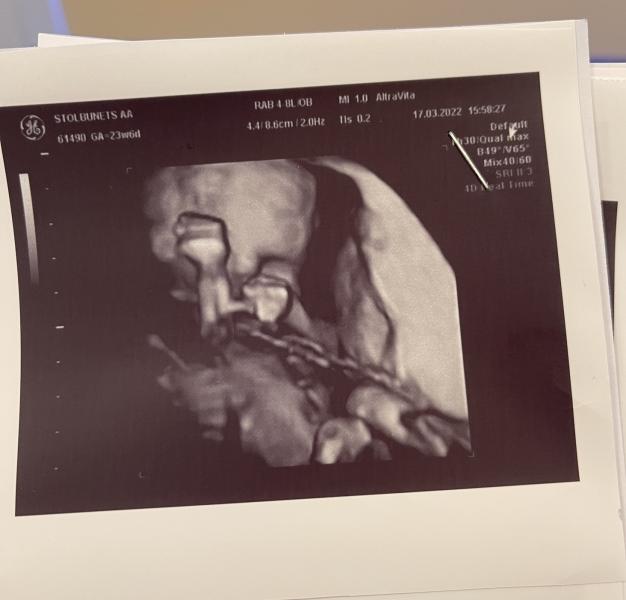

Продолжение чуть позже напишу. На третьем фото 23 недельки ❤️ а на первом Давидик улыбается 💙